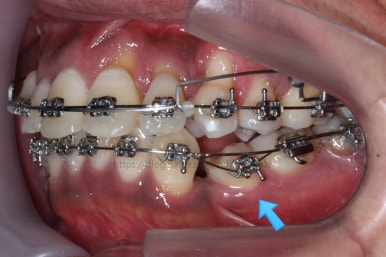

화살표를 보면 작은 어금니 하나가 아래로 꺼져있는데, 이 녀석 때문에 애를 먹었네요. 훨씬 치료가 빨리 끝날 수 있었는데 이 치아가 워낙 잘 안움직이는 바람에 2년 개월정도로 치료기간이 많이 걸린 편이었어요.

대신 위쪽 아래 작은 어금니가 애를 먹이고 있어요. 낚시줄처럼 부여매고 끌어올리는게 보이실거에요.

뼈에 단단히 붙어 안움직이는 경우를 "유착치아"라고 표현하는데, 유착치아라면 해당 치아를 움직이는 것을 포기했어야 했어요.

그래도 조금씩이라도 움직이고 있어서 계속 시도했습니다.